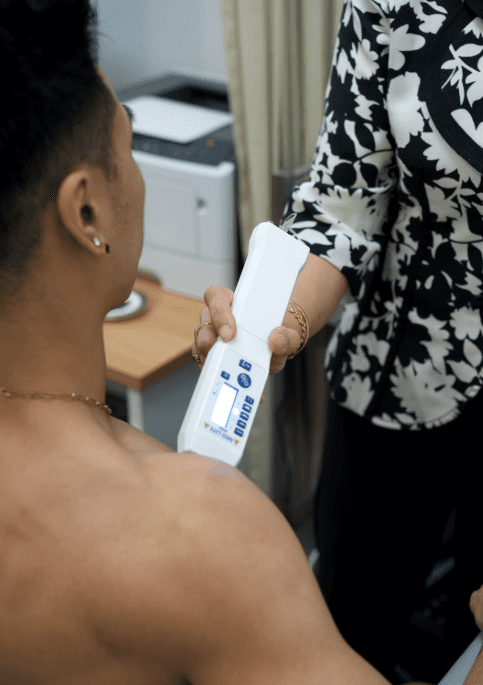

Low Level Laser Therapy (LLLT) also known as Photobiomodulation Therapy (PBMt) is the application of red and near infrared light over injuries to stimulate cellular repair. LLLT is highly effective, completely safe treatment in Melbourne, Victoria. It is painless, and has no effect on normal tissues. LLLT treats the underlying cause of the injury unlike pain medication which just masks the pain. It is a treatment modality supported by research from reputable institutions including Harvard University and NASA. LLLT is an evidence-based therapy for soft tissue injuries, such as shoulder impingement.

Low Level Laser Therapy (LLLT), also known as Photobiomodulation Therapy (PBMT), is a gentle, evidence-based treatment that targets the underlying cause of shoulder impingement: inflammation and micro-tears affecting the rotator cuff tendons and bursa. It promotes healing without mechanical stress to already irritated shoulder structures.

How LLLT Supports Healing

LLLT uses red and near-infrared light to restore balance to the inflammatory process and stimulate tendon and bursal repair by:

- Improving circulation and oxygenation

- Enhancing lymphatic drainage

- Reducing inflammation and oxidative stress

- Increasing cellular energy (ATP)

- Supporting regeneration of rotator cuff tissues

All without loading or stressing the shoulder joint.